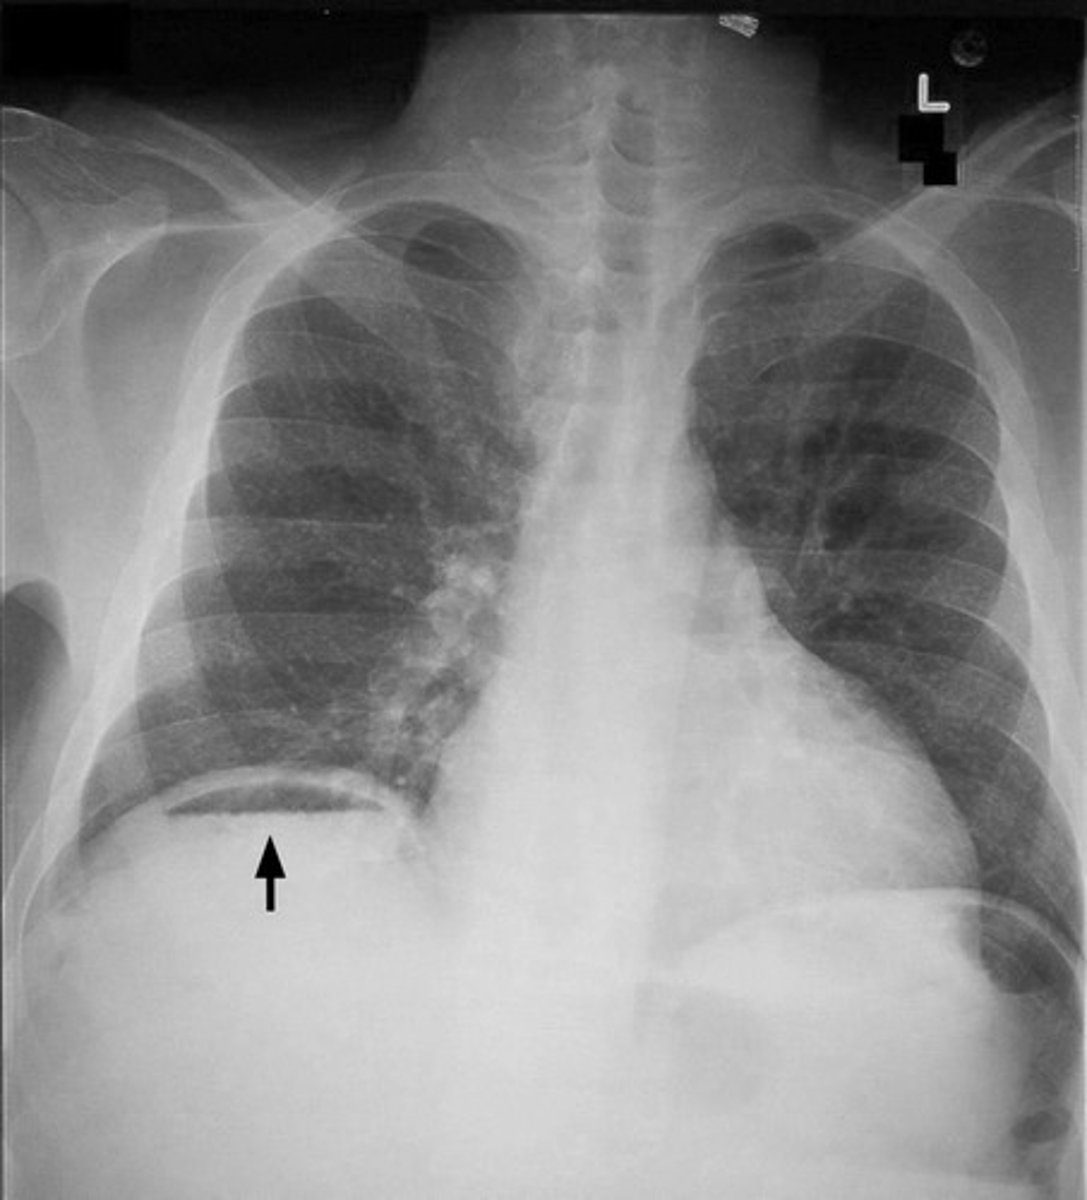

pneumoperitoneum

Free air or gas in the peritoneal cavity